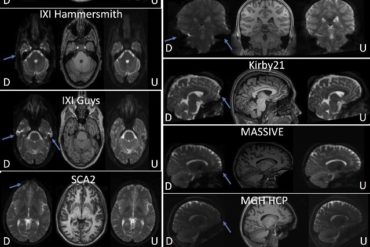

Vanderbilt and VUMC researchers have created a technique that corrects distortions in MRI images, which helps researchers and radiologists to...